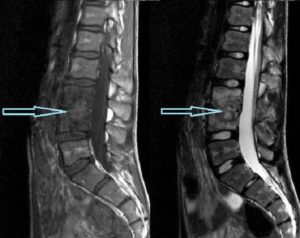

нажми на картинку для увеличения МРТ грудного отдела позвоночника. Красной стрелкой обозначена зона спондилодисцита. Методы диагностики спондилодисцита: